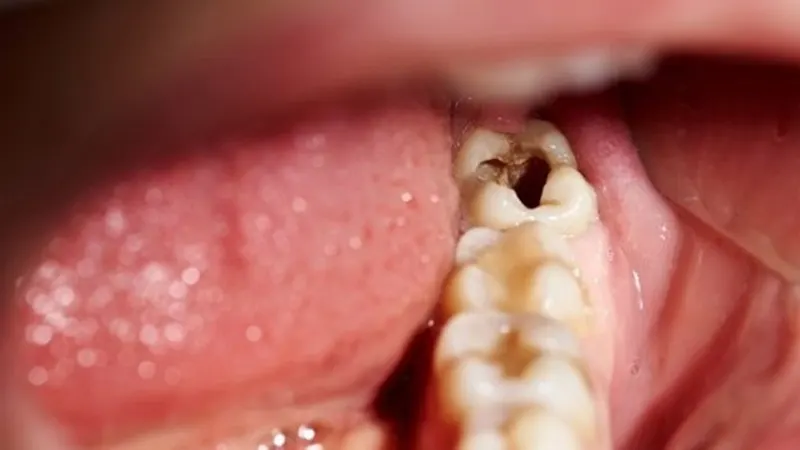

Dấu hiệu nhận biết răng khôn bị sâu

Răng khôn bị sâu ở giai đoạn đầu rất khó nhận biết. Tình trạng này không được xử lý kịp thời sẽ khiến sâu răng phát triển nặng hơn, lây lan sang các răng khác. Răng khôn bị sâu có thể xuất hiện các triệu chứng như:

- Cảm giác đau nhức và nhạy cảm ở vùng nướu.

- Nướu mềm, sưng đỏ và chảy máu.

- Xuất hiện chất dịch màu trắng xung quanh răng.

- Hơi thở có mùi hôi hoặc vị chua khó chịu.

- Đau, sưng và cứng hàm.

- Khó khăn trong việc mở miệng, nhất là thở và nói chuyện.